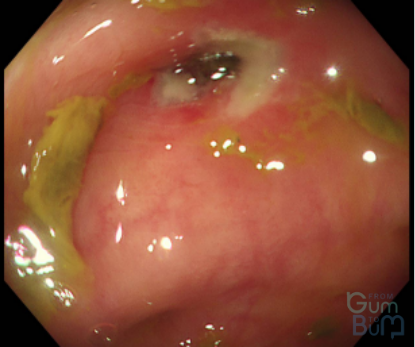

Which classification can be used in Esophageal Candidiasis?

candidia